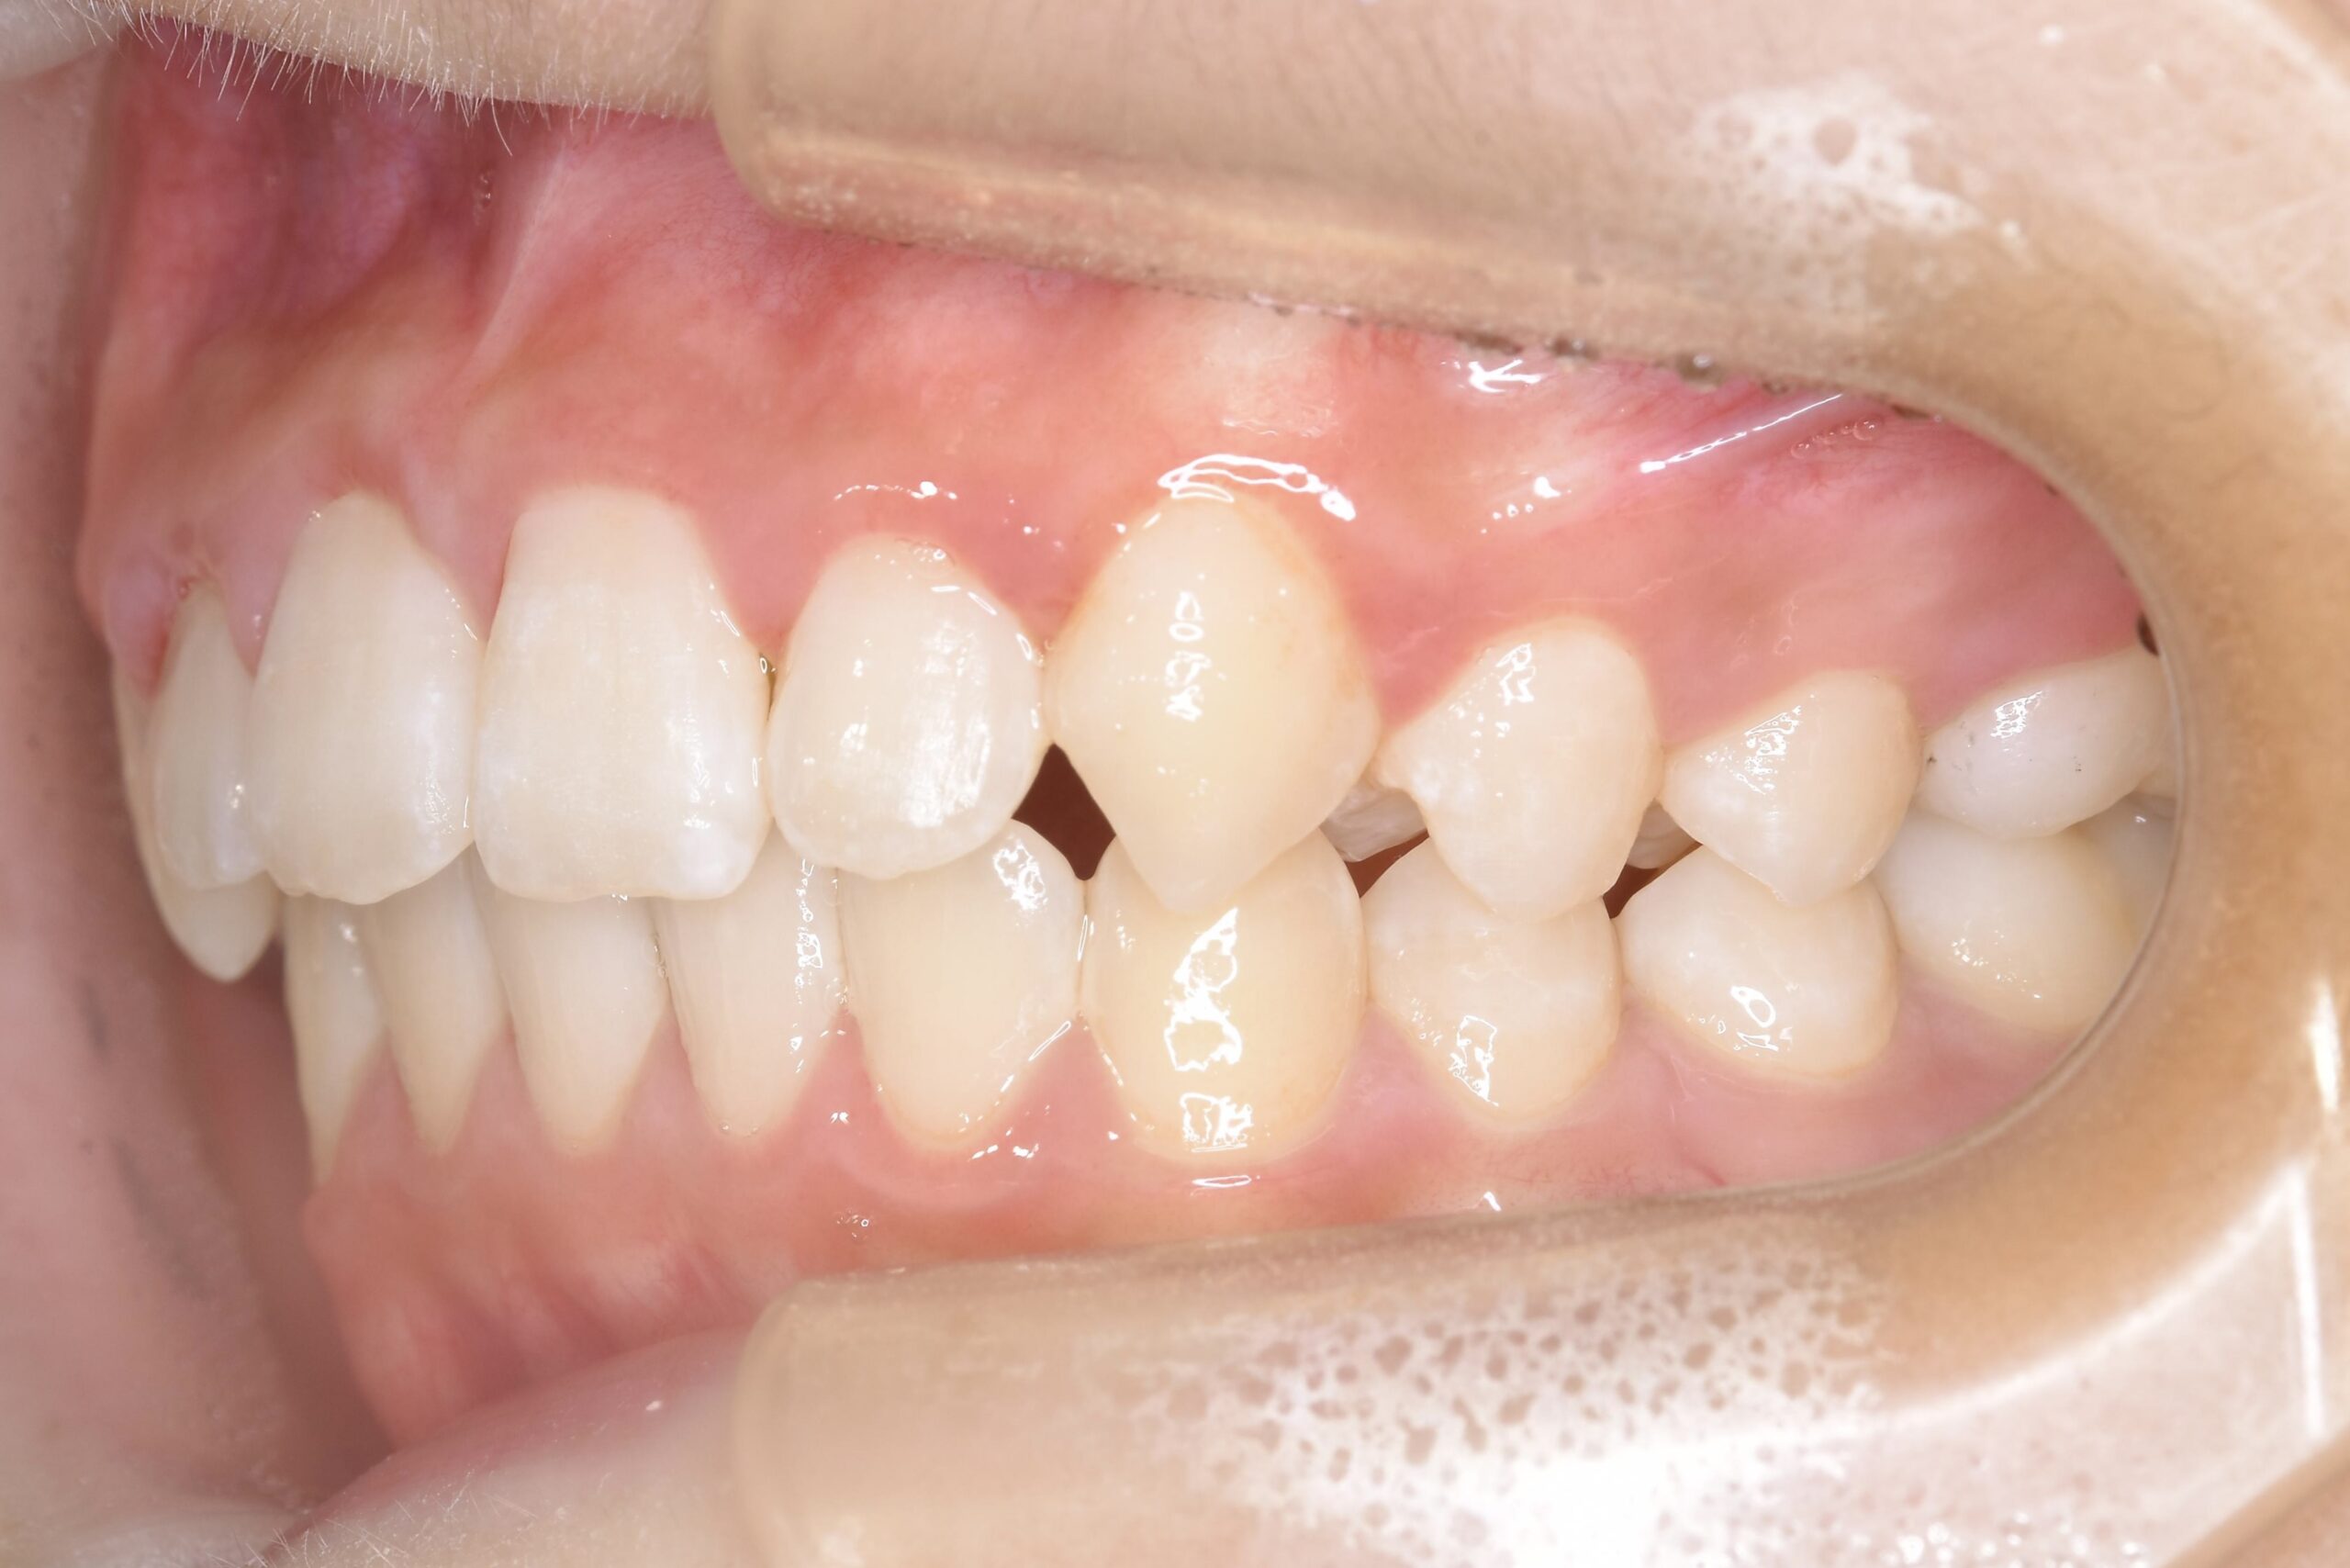

AFTER

主訴 通っている歯医者で矯正した方がいいと言われて気になっている。下の前歯がでこぼこしている。

診断名・主な症状 下顎前歯の叢生を伴う過蓋咬合

年齢 7歳

治療内容 上下の歯並びの幅を拡げつつ、前歯の関係を改善しました。

使用装置 急速拡大装置

リンガルアーチ

機能的矯正装置(マイオブレース)

抜歯部位 抜歯なし

治療期間 2年 + 後戻り止め期間(3年 )

通院回数 20回

費用 50万円程度(税別)  29331

リスク・副作用 痛み、歯肉退縮、歯根吸収、抜歯に伴う出血や腫れが生じることがあります。